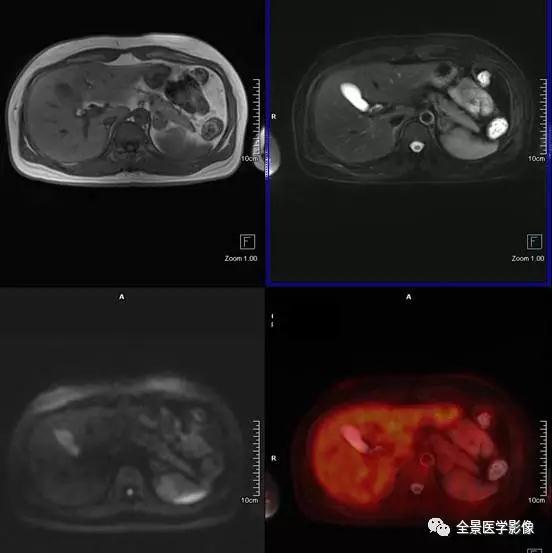

PET/MRI

肾上腺

肾上腺腺瘤

◆ 案例:中年男性,无任何症状。左侧肾上腺结合部见一长径约 1.8 cm 结节,FDG 稍摄取,考虑为肾上腺腺瘤。

点评:

根据是否有功能,可分为无功能性和功能性腺瘤。一般来说,偶然发现的肾上腺腺瘤都是无功能性的。对于无功能性腺瘤,注意定期复查。功能性腺瘤需要专科医生进行评估,最好是具备诊断肾上腺肿瘤丰富经验的放射科医师、内分泌医生和外科医生组成的评估小组。

髓样脂肪瘤

◆ 案例:中年女性,左侧肾上腺见一大小约 1.9 cm×2.1 cm 的类圆形异常信号灶,信号不均匀,内含脂肪信号,考虑为髓样脂肪瘤。

本病很少出现临床症状,多在体检时偶然发现。如肿瘤较大压迫邻近组织器官或瘤内出血坏死,可引起不适症状。但对于直径较小且无临床症状者应随访观察。